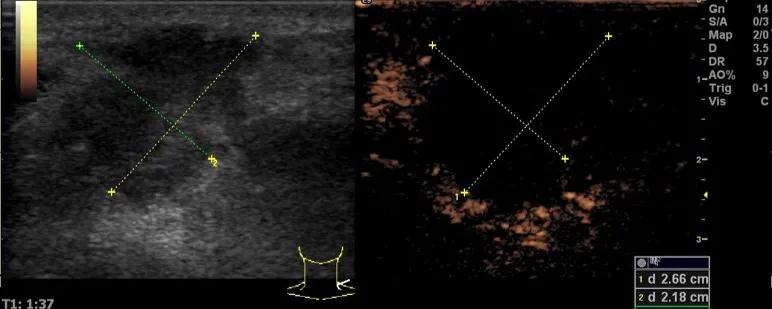

随后,徐栋教授进一步分享了五个临床实战病例,带来了更直观的热消融治疗经验。第一个病例是62岁肺癌患者,术后1年余发现双侧锁骨上淋巴结复发,侵犯神经,存在静脉回流、淋巴回流障碍,肿胀、疼痛非常明显。影像显示患者淋巴结边界不清、形态不规则,存在浸润,血流强化增强。由于患者在系统治疗后进展,且主要目的缓解症状、减瘤。局麻下行热消融术,从后向前逐层消融,热消融之后超声造影即刻评估显示完全充盈缺损,完全覆盖病灶。

(病例1图例)